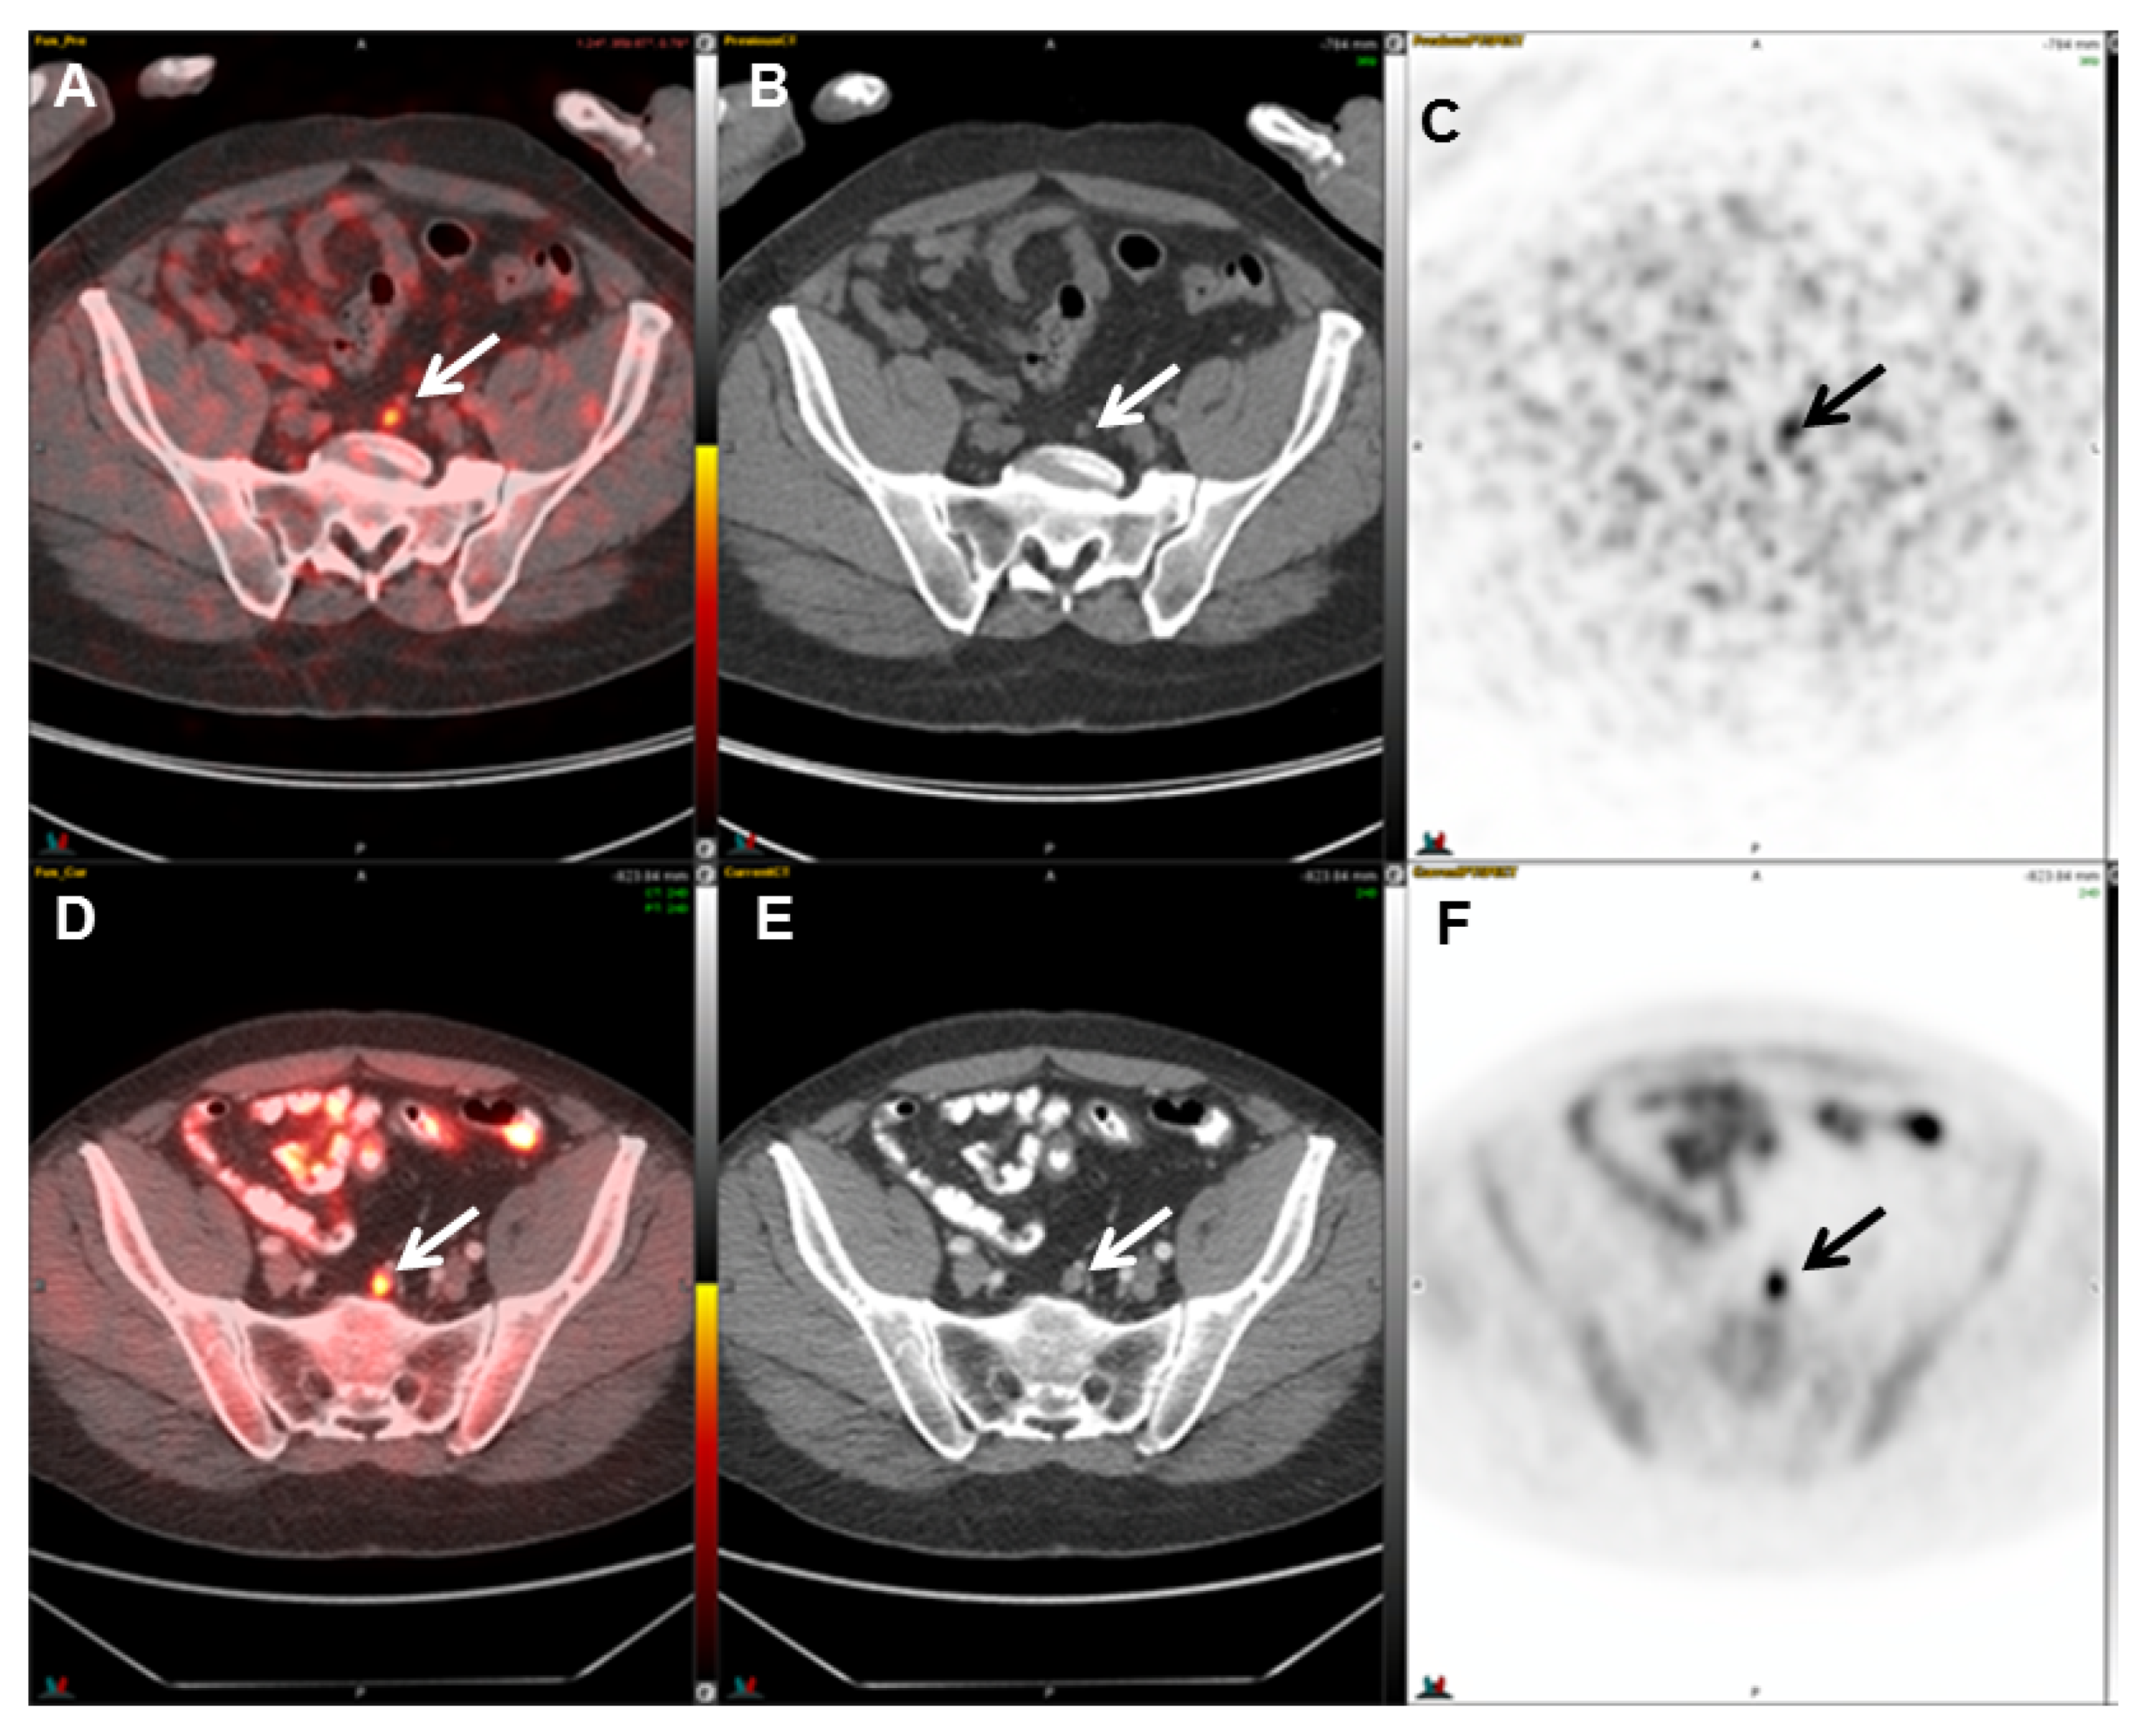

2.4. 18F-Fluciclovine (FACBC) PET

- Gusman, M.; Aminsharifi, J.A.; Peacock, J.G.; Anderson, S.B.; Clemenshaw, M.N.; Banks, K.P. Review of 18F-Fluciclovine PET for Detection of Recurrent Prostate Cancer. Radiographics 2019, 39, 822–841. [Google Scholar] [CrossRef]

- Savir-Baruch, B.; Odewole, O.; Alaei Taleghani, P.; Master, V.; Nieh, P.; Halkar, R.; Jani, A.; Goodman, M.; Yu, W.; Schster, D. Anti-3-[F18] FACBC uptake pattern in the prostate affects positive predictive value and is associated with the presence of brachytherapy seeds. J. Nucl. Med. 2013, 54, 346. [Google Scholar]